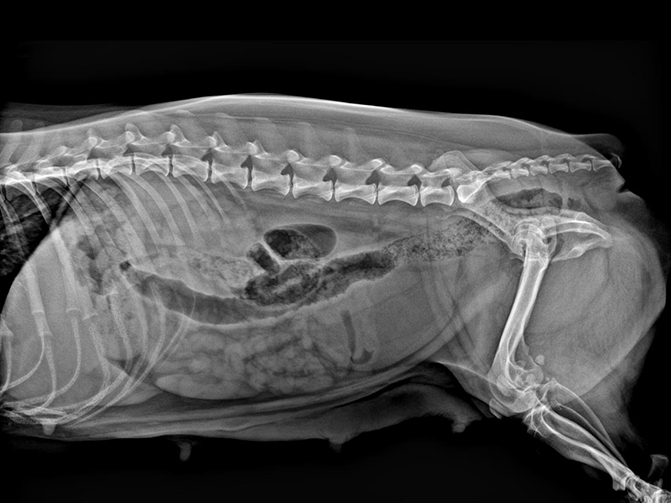

VET-528